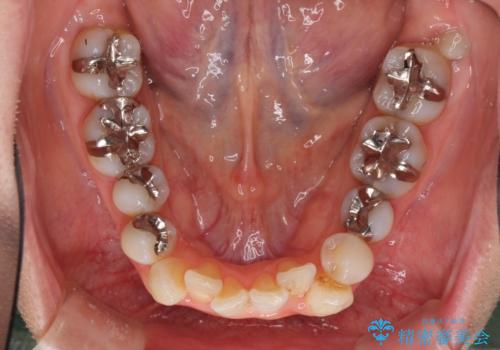

- 前歯のデコボコと矮小歯、更には痛みを感じる奥歯のむし歯を気にして来院された患者様です。

奥歯には根管治療が必要な歯があり、上顎側切歯は左右ともに矮小歯でした。

上下前歯のデコボコはワイヤーでもインビザラインでも対応可能でしたが、補綴治療が多く必要となることから、インビザラインでの矯正治療を行いながら、並行して補綴治療を行うこととしました。

まずは根管治療を行った上で矯正治療用の仮歯を装着し、矯正治療後半に補綴治療を並行して行うこととしました。